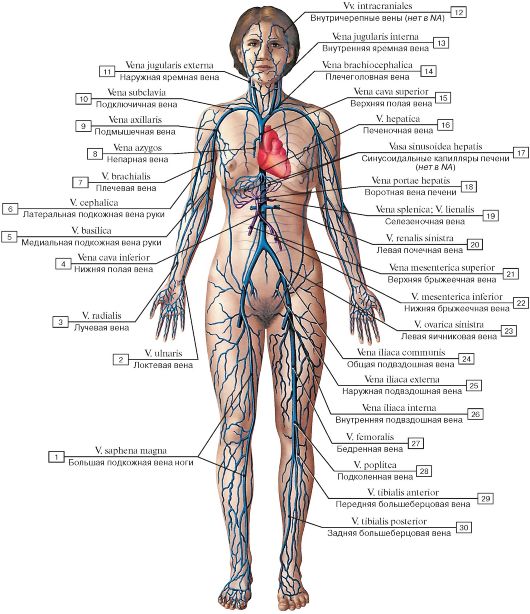

Анатомия человека: кровеносная система и её связь со скелетом